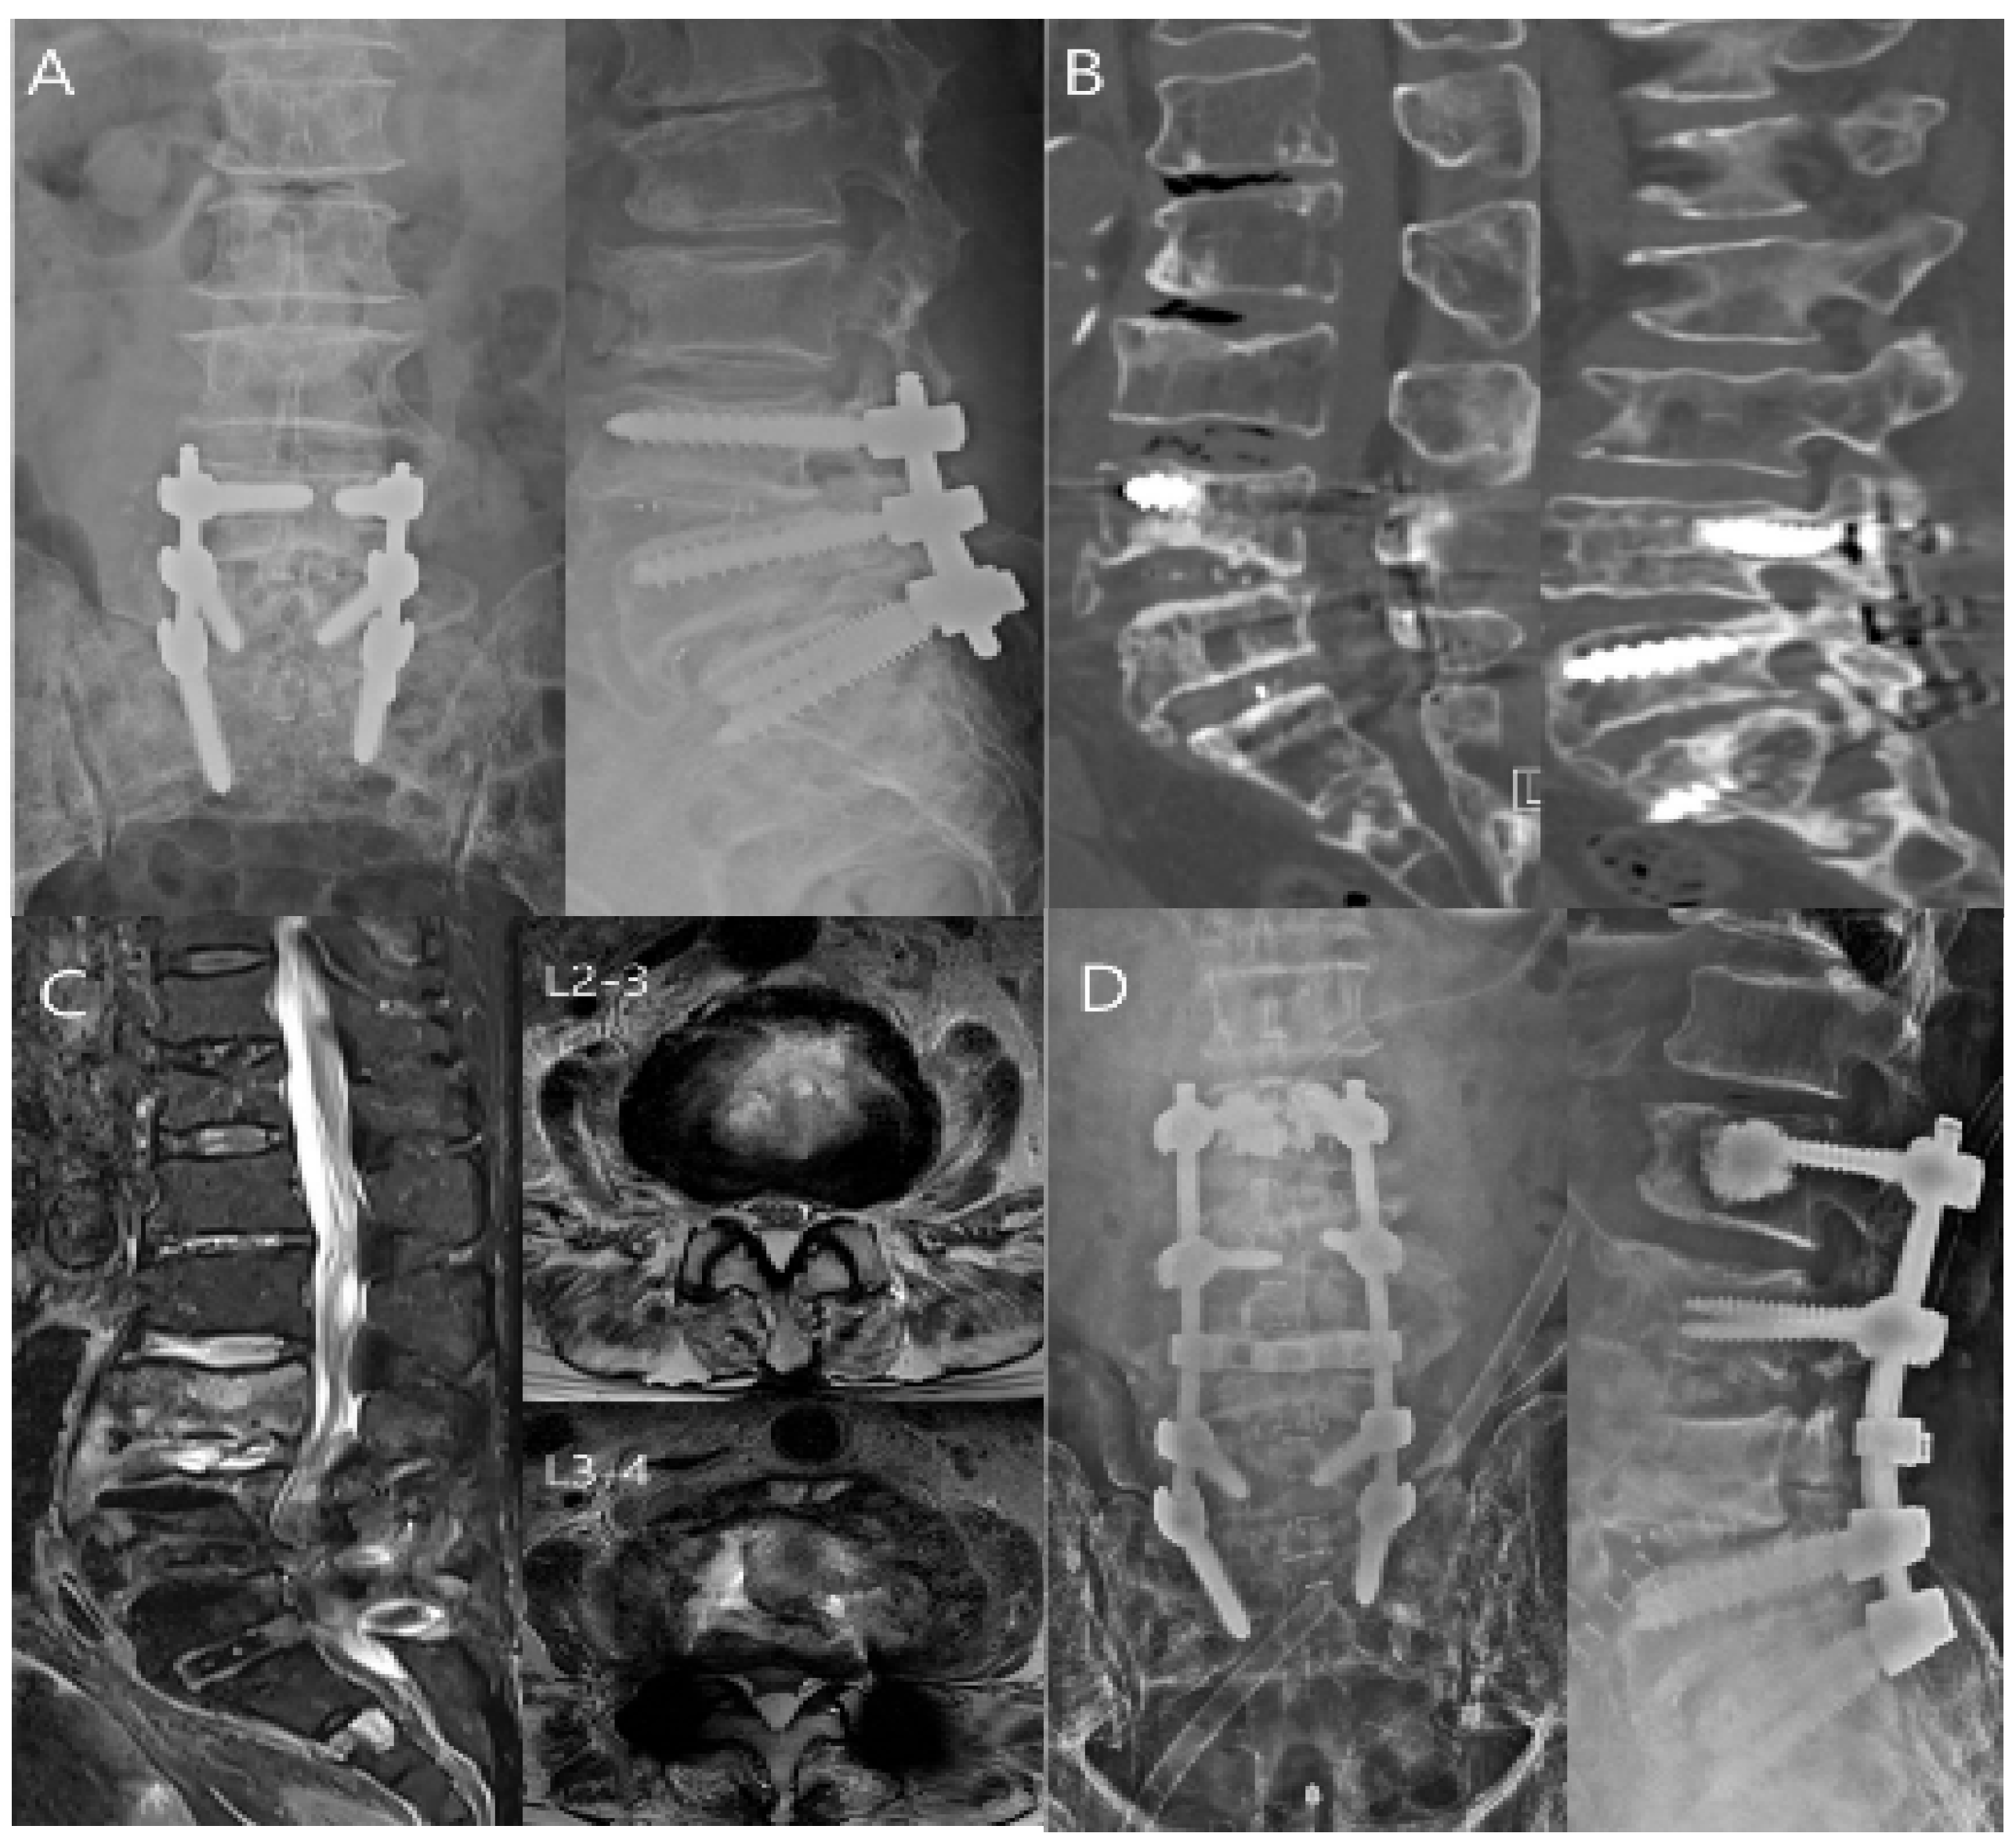

7.3. Imaging Tests

9. Treatment of the Spinal Infection